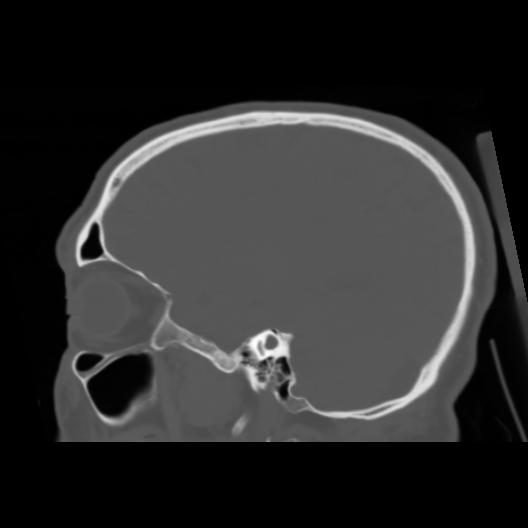

6 CEREBRO,,Sagittal,3.000,CEREBRO,Sagittal,